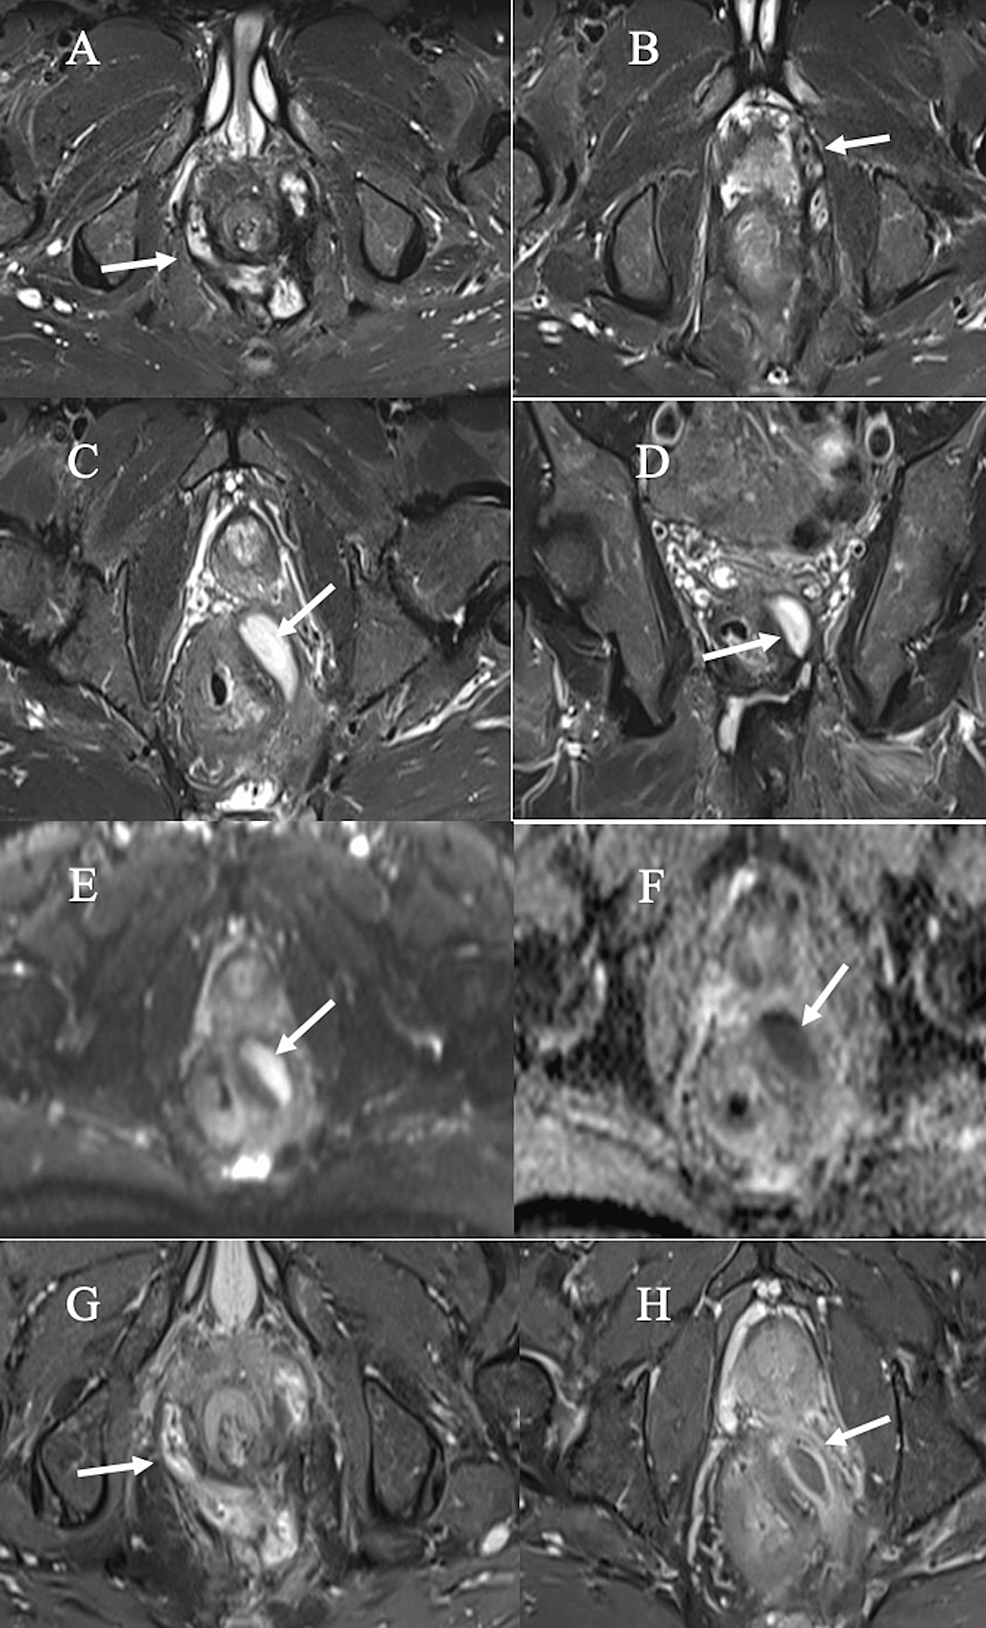

Horseshoe fistula in the intersphincteric plane on an axial T2weighted Horseshoe Fistula Images Horseshoe extensions may be ischioanal, intersphincteric, or supralevator. When you describe a fistula, it is important to mention the following characteristics: An anal fistula is usually a side effect of an anal abscess, an infected wound that drains pus from your anus. A ‘horseshoe’ fistula indicates a tract crosses midline within the intersphincteric space. Perianal fistulas can be associated with. Horseshoe Fistula Images.

Horseshoeshaped intersphincteric fistula with positive inflammation Horseshoe Fistula Images An anal fistula is usually a side effect of an anal abscess, an infected wound that drains pus from your anus. Perianal fistulas can be associated with significant morbidity, and knowledge of how they arise, how to image them, how to describe them, and how to classify them on radiologic images is paramount to ensure appropriate management. Position of the. Horseshoe Fistula Images.